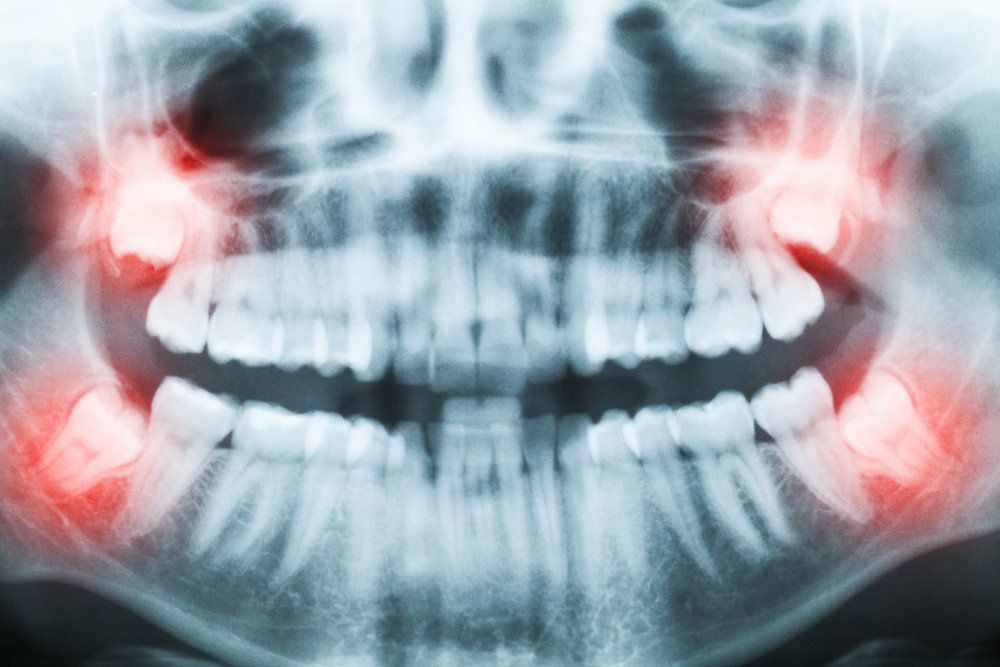

Dr. Berbari will perform a routine examination with a panoramic x-ray to determine if your wisdom teeth will need to be removed. If there are signs of impaction or if the wisdom teeth appear to be growing too close to the adjacent teeth, we can schedule your surgery. The removal procedure can typically be completed in about one hour, and most patients will require two to three days of rest following the appointment. Dr. Berbari will let you know if there are any special precautions for your case, such as fasting, but most patients do not need to take any preparatory measures.

Wisdom teeth usually appear in the mouth when a patient is in their late teens or early twenties. If their growth is normal and does not disrupt the rest of your tooth alignment, you may not have to worry about them. However, often because of the lack of space, wisdom teeth become inclined or stuck underneath the gum line. This is called an impacted wisdom tooth and it needs to be extracted before damage is caused to the rest of your mouth.